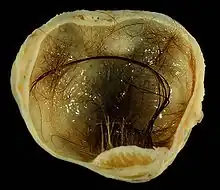

Immature (solid) teratoma

Immature, or solid, teratomas are the most common type of ovarian germ cell tumor, making up 40–50% of cases. Teratomas are characterized by the presence of disorganized tissues arising from all three embryonic germ layers: ectoderm, mesoderm, and endoderm; immature teratomas also have undifferentiated stem cells that make them more malignant than mature teratomas (dermoid cysts). The different tissues are visible on gross pathology and often include bone, cartilage, hair, mucus, or sebum, but these tissues are not visible from the outside, which appears to be a solid mass with lobes and cysts. Histologically, they have large amounts of neuroectoderm organized into sheets and tubules along with glia; the amount of neural tissue determines the histologic grade. Immature teratomas usually only affect one ovary (10% co-occur with dermoid cysts) and usually metastasize throughout the peritoneum. They can also cause mature teratoma implants to grow throughout the abdomen in a disease called growing teratoma syndrome; these are usually benign but will continue to grow during chemotherapy, and often necessitate further surgery. Unlike mature teratomas, immature teratomas form many adhesions, making them less likely to cause ovarian torsion. There is no specific marker for immature teratomas, but carcinoembryonic antigen (CEA), CA-125, CA19-9, or AFP can sometimes indicate an immature teratoma.[32]

Stage I teratomas make up the majority (75%) of cases and have the best prognosis, with 98% of patients surviving five years; if a Stage I tumor is also grade 1, it can be treated with unilateral surgery only. Stage II though IV tumors make up the remaining quarter of cases and have a worse prognosis, with 73–88% of patients surviving five years.[32]

Mature teratoma (dermoid cyst)

Mature teratomas, or dermoid cysts, are rare tumors consisting of mostly benign tissue that develop after menopause. The tumors consist of disorganized tissue with nodules of malignant tissue, which can be of various types. The most common malignancy is squamous cell carcinoma, but adenocarcinoma, basal-cell carcinoma, carcinoid tumor, neuroectodermal tumor, malignant melanoma, sarcoma, sebaceous tumor, and struma ovarii can also be part of the dermoid cyst. They are treated with surgery and adjuvant platinum chemotherapy or radiation.[32]